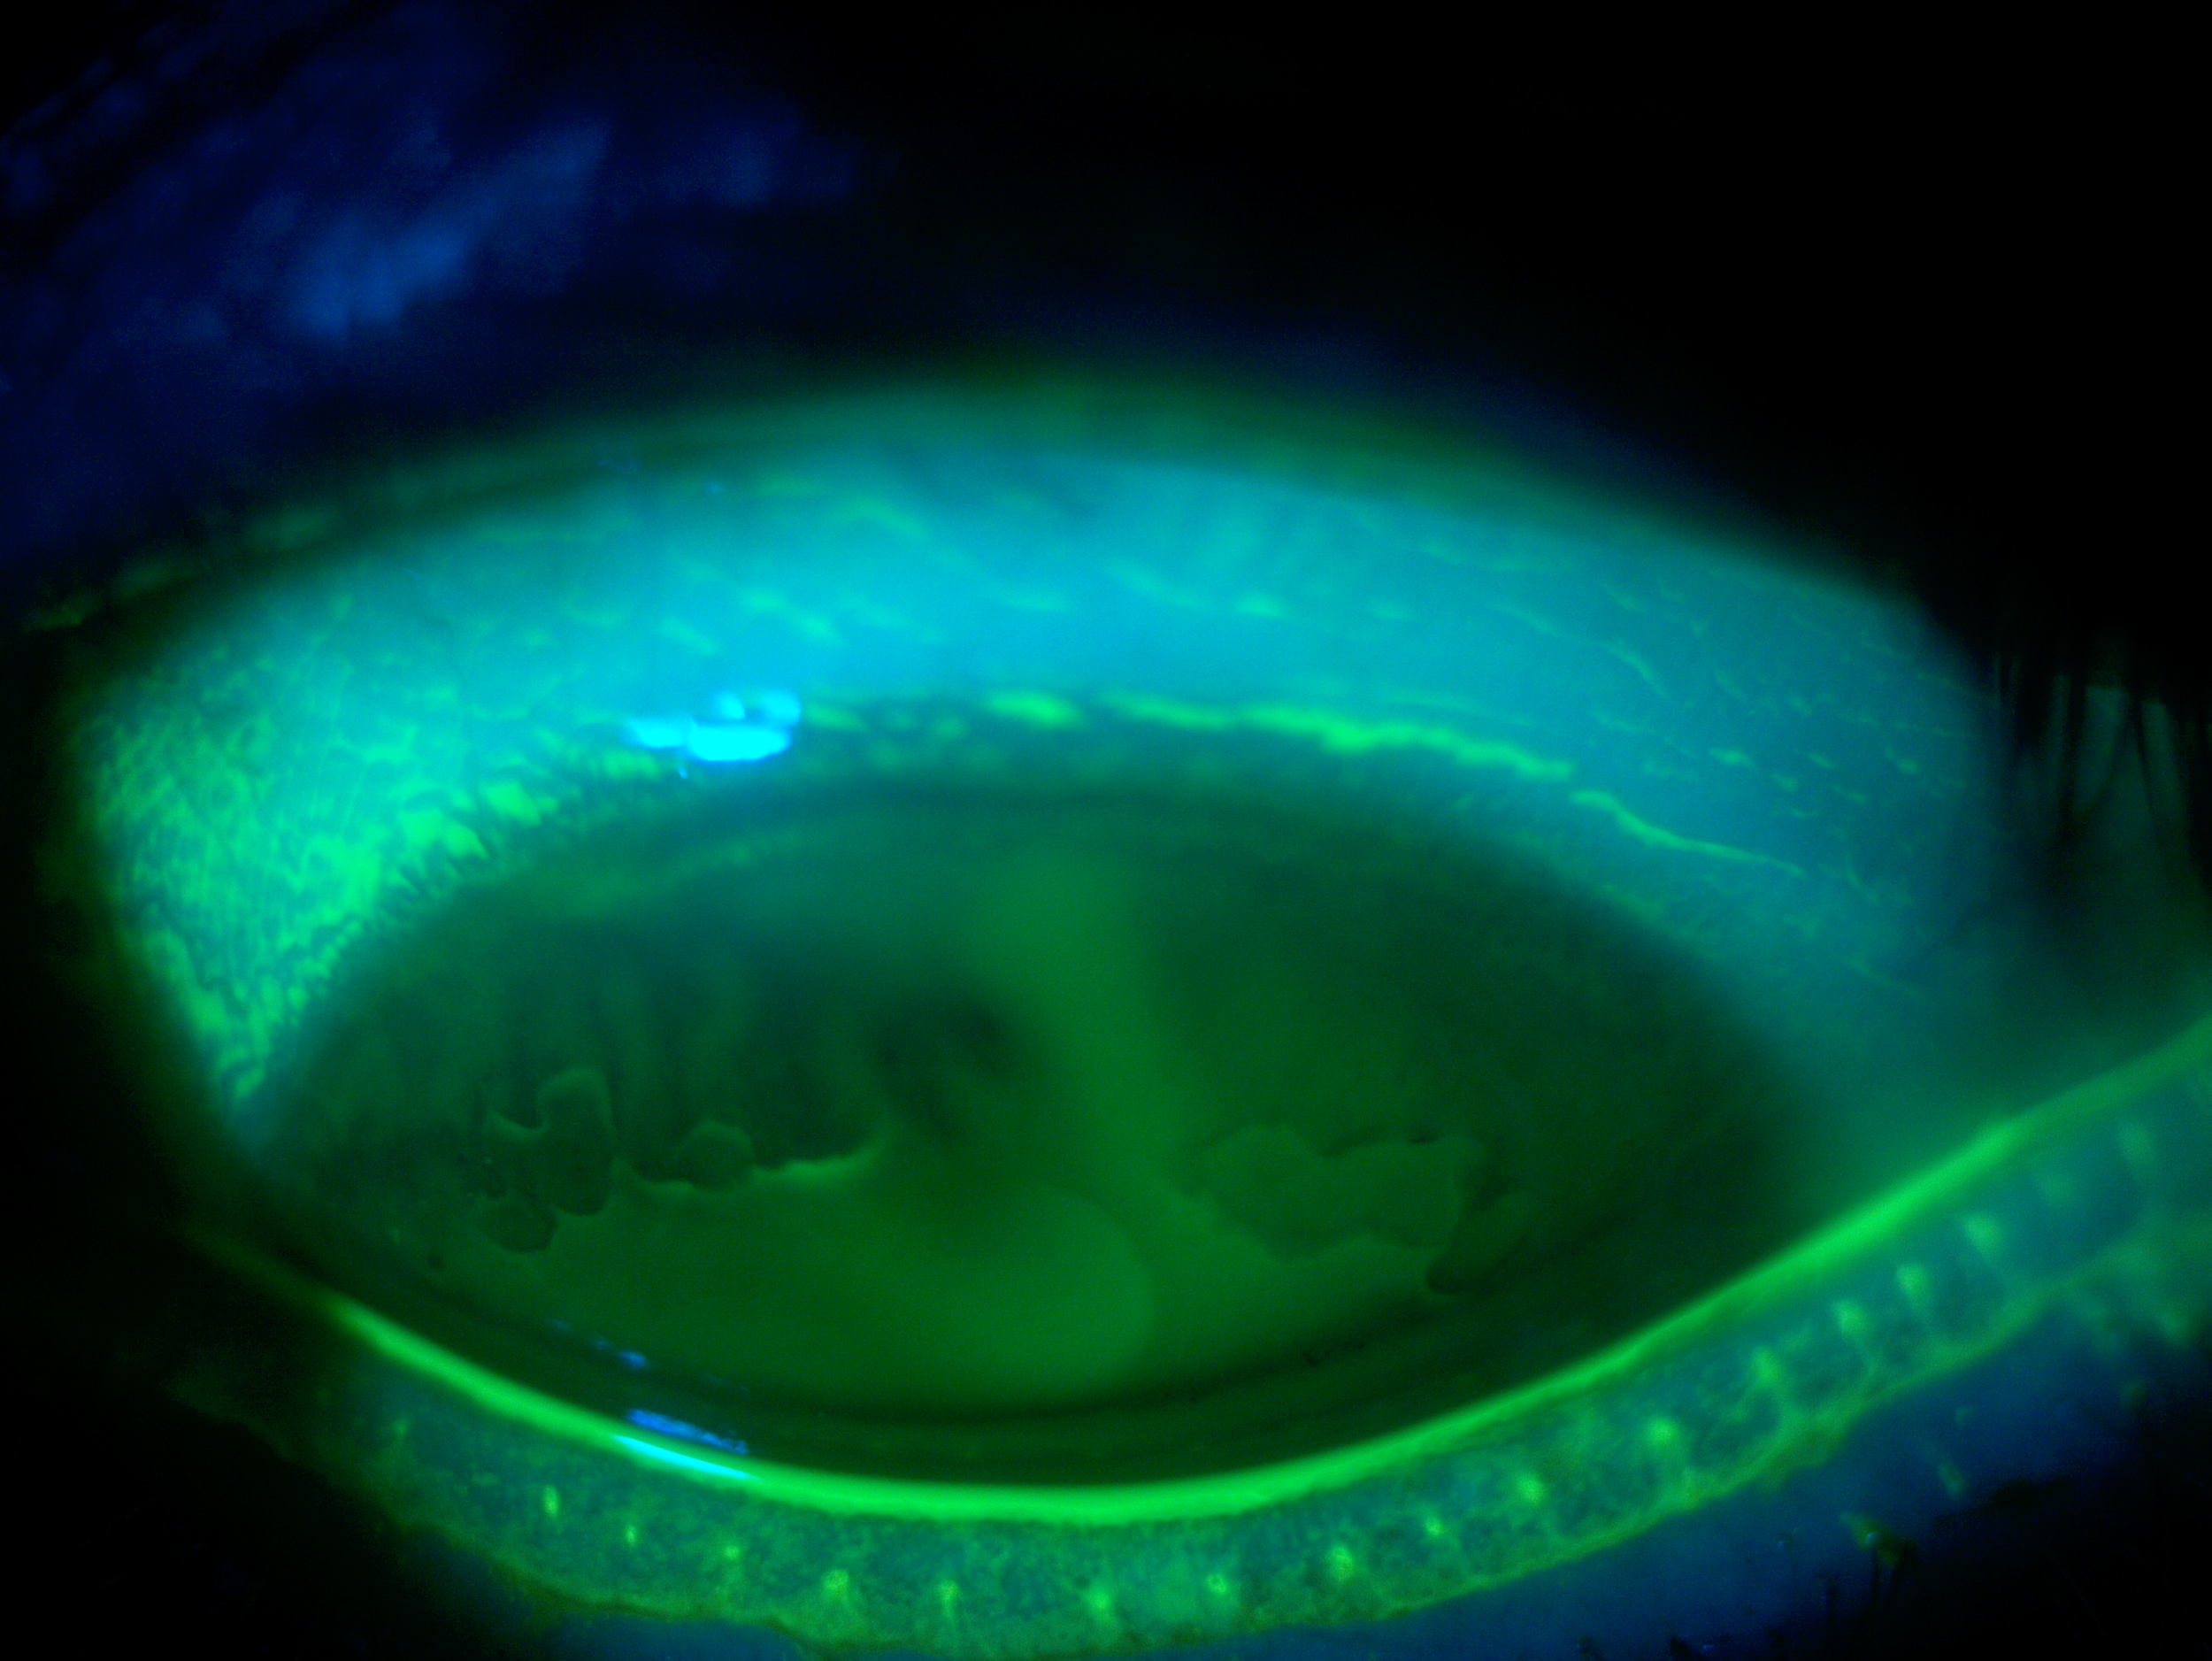

Rather than sitting directly on the eye like a traditional soft lens, scleral lenses only touch the sclera (the white part of the eye) and vault entirely over the cornea (the front of your eye - a clear layer of tissue that covers your iris, pupil and lens). This vault - the space between the contact lens and your cornea - is filled with fluid and creates a new, perfect focusing surface.

By vaulting over the eye with fluid, we are able to manage complicated eye conditions such as astigmatism, keratoconus, corneal transplants, severe dry eye, corneal scarring, LASIK complications and more. These lenses can be life changing.

At a scleral lens consultation, we will first learn and discuss your eye health history, take profilometry and topography scans, and discuss your needs. If you are new to scleral lenses, we will place a “demo” scleral lens on your eye(s) to check the vision potential of your eyes, as well as to see if your eyes feel better if your condition is related to dry eyes. If we determine that you are a candidate and proceed with scleral lenses, our doctor Dr. Seif then orders a unique, custom designed lens and adjusts it until the most optimal vision and fit is achieved.

For established wearers, we would assess your current prescription and utilize anterior segment OCT to assess the fit of your current lenses. We may also run aberrometry measurements to see if you would benefit from higher-order aberration correction. We would determine if your current lens design is appropriate healthwise, or if you would benefit from a different lens design.

When customizations are needed or when conventionals fall short. Includes scan-based, freeform, and EyeFitPro (impression molding). 40,000 data points are collected to create a custom fit lens.

For the ultimate precise fit and full customization options utilizing impression molding (EyePrintPro). 80,000 points of data are collected to create a truly unique scleral lens.